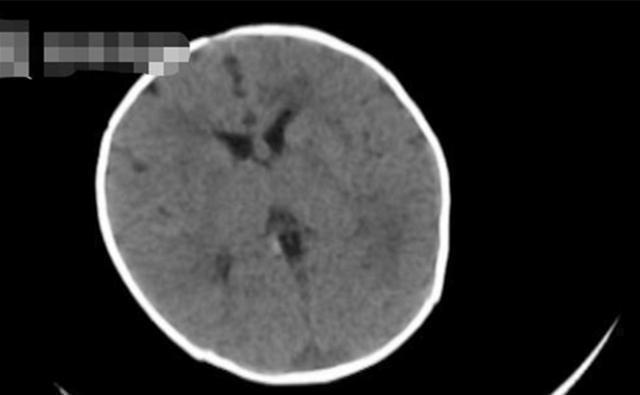

两个孩子送医仔细检查后,居然发现得的全是“脑出血”?这让很多人都难以置信,这种大多只会出现在老人身上的疾病,为什么会在几个月大的孩子身上出现?

原来,宝宝们之所以会出现“脑出血”的情况,主要是因为体内缺乏一种维生素,即“维生素K”。

维生素K是一种有助于血凝的维生素,孩子如果体内缺乏这种维生素,就会有大几率患上“维生素K缺乏症”,这种缺乏症导致的后果就是孩子容易得一系列的“出血性疾病”。

在这其中最危险的也莫过于“脑出血”了。